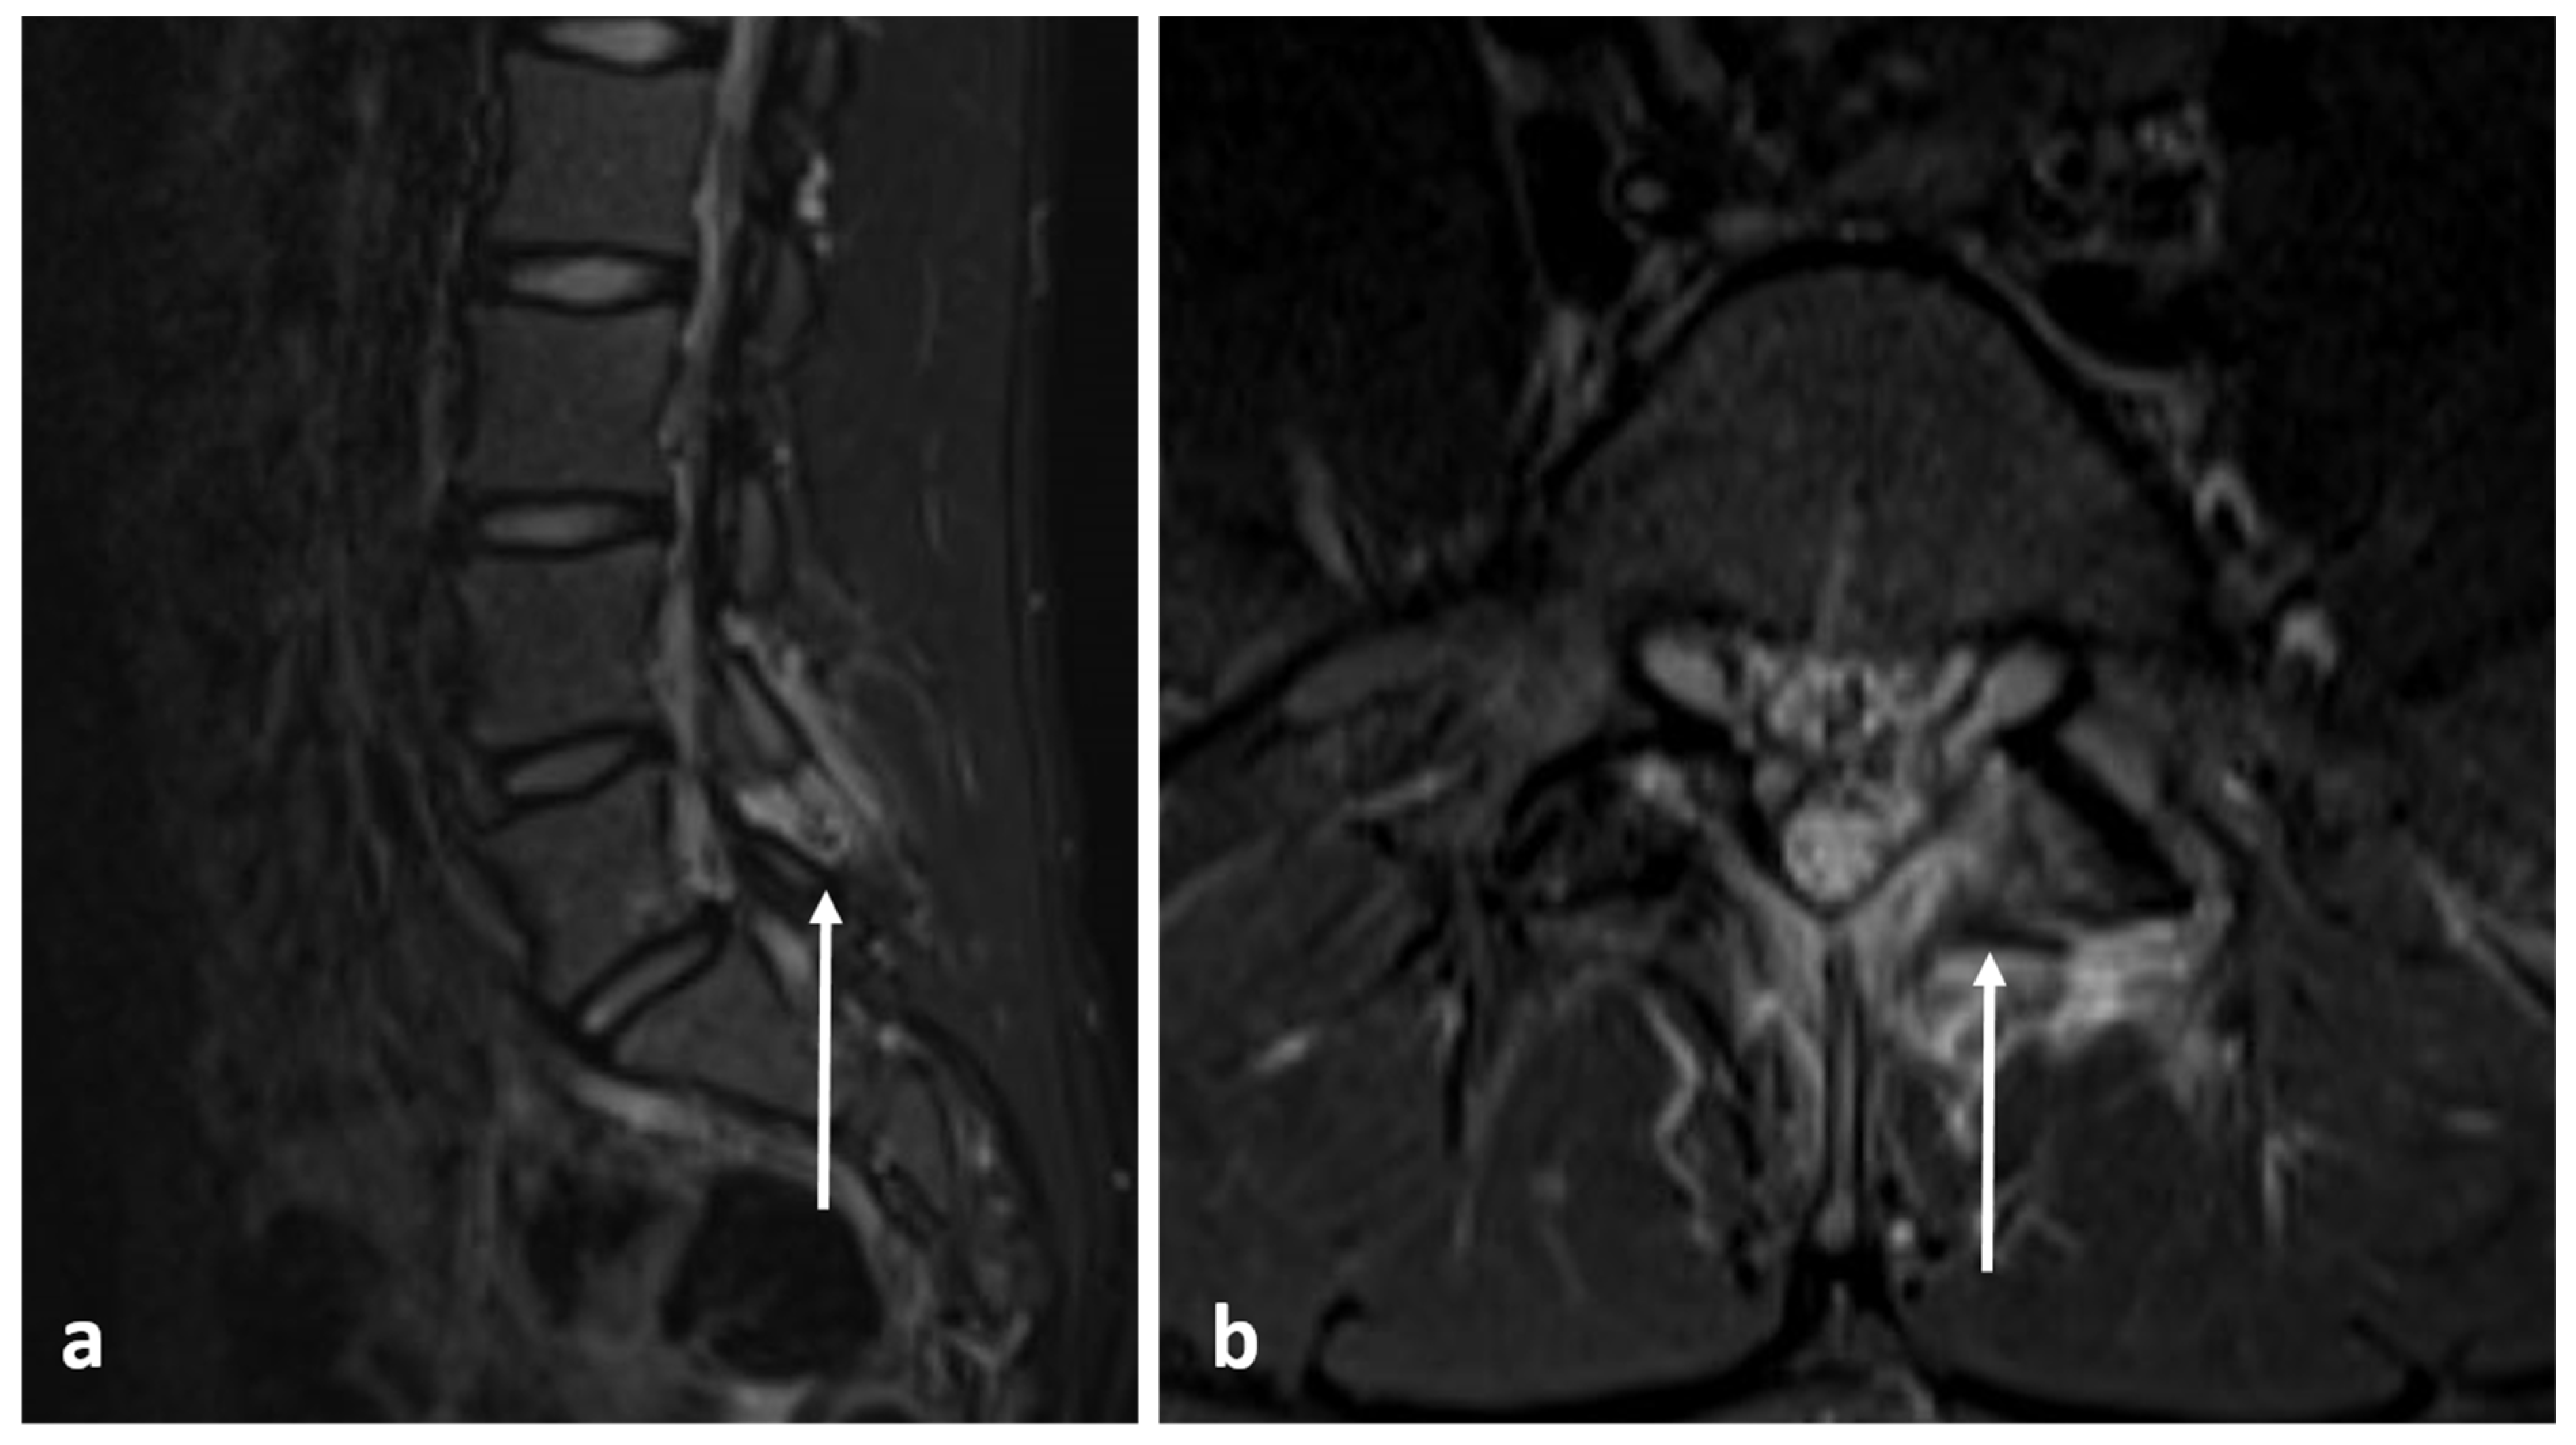

3.9. Aneurysmal Bone Cyst

| Aneurysmal bone cyst | Expansile lytic lesion with internal bone septations. | Fluid—fluid levels within the cysts, high T1 signal within layering fluid content due to haemorrhage. |